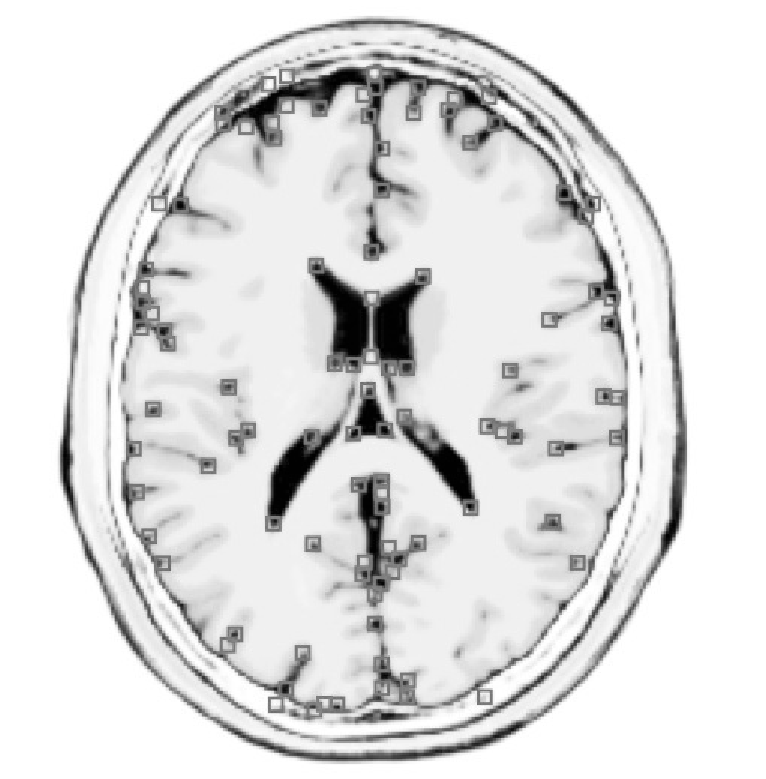

for some (typically set to ). Corners are then defined as the local maxima of the cornerness (as illustrated on Fig. 1), that is,

The databases used in our experiments are a T2-modulation volume MRI cut into slices along the directions, from the Brainweb simulator [6] and the ORL Database of faces [11]. In order to test the ISH, three sets of transformations have been applied on these images: (i) 9 rotations of angles between and , (ii) scalings of factors between and , (iii) and 9 random combinations of these rotations and scalings. A schematic illustration of the face image manifold (that has a polar representation for each image) is shown in Fig. 1.